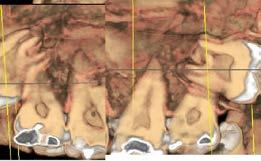

Prótese Protocolo Digital: O uso da Sequência de Fibonacci em implante dentário

52 Cirurgia do Terceiro Molar: O que precisa saber